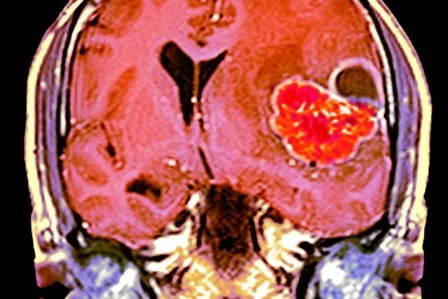

A MRI scan through the head of a 48-year-old male patient with a glioblastoma

Colored coronal magnetic resonance imaging (MRI) scan

What you are seeing:

Colored coronal magnetic resonance imaging (MRI) scan through the head of a 48-year-old male patient with a glioblastoma (red), with surrounding oedema (fluid) that is compressing the left ventricle (at right). A glioblastoma is a particularly malignant brain cancer that arises from the supporting glial cells in the brain. Treatment is with a combination of surgery and radiotherapy, but the prognosis is poor.